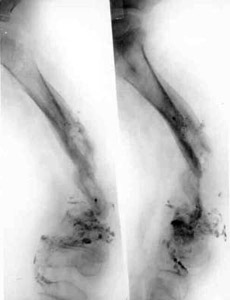

Results of treatment.